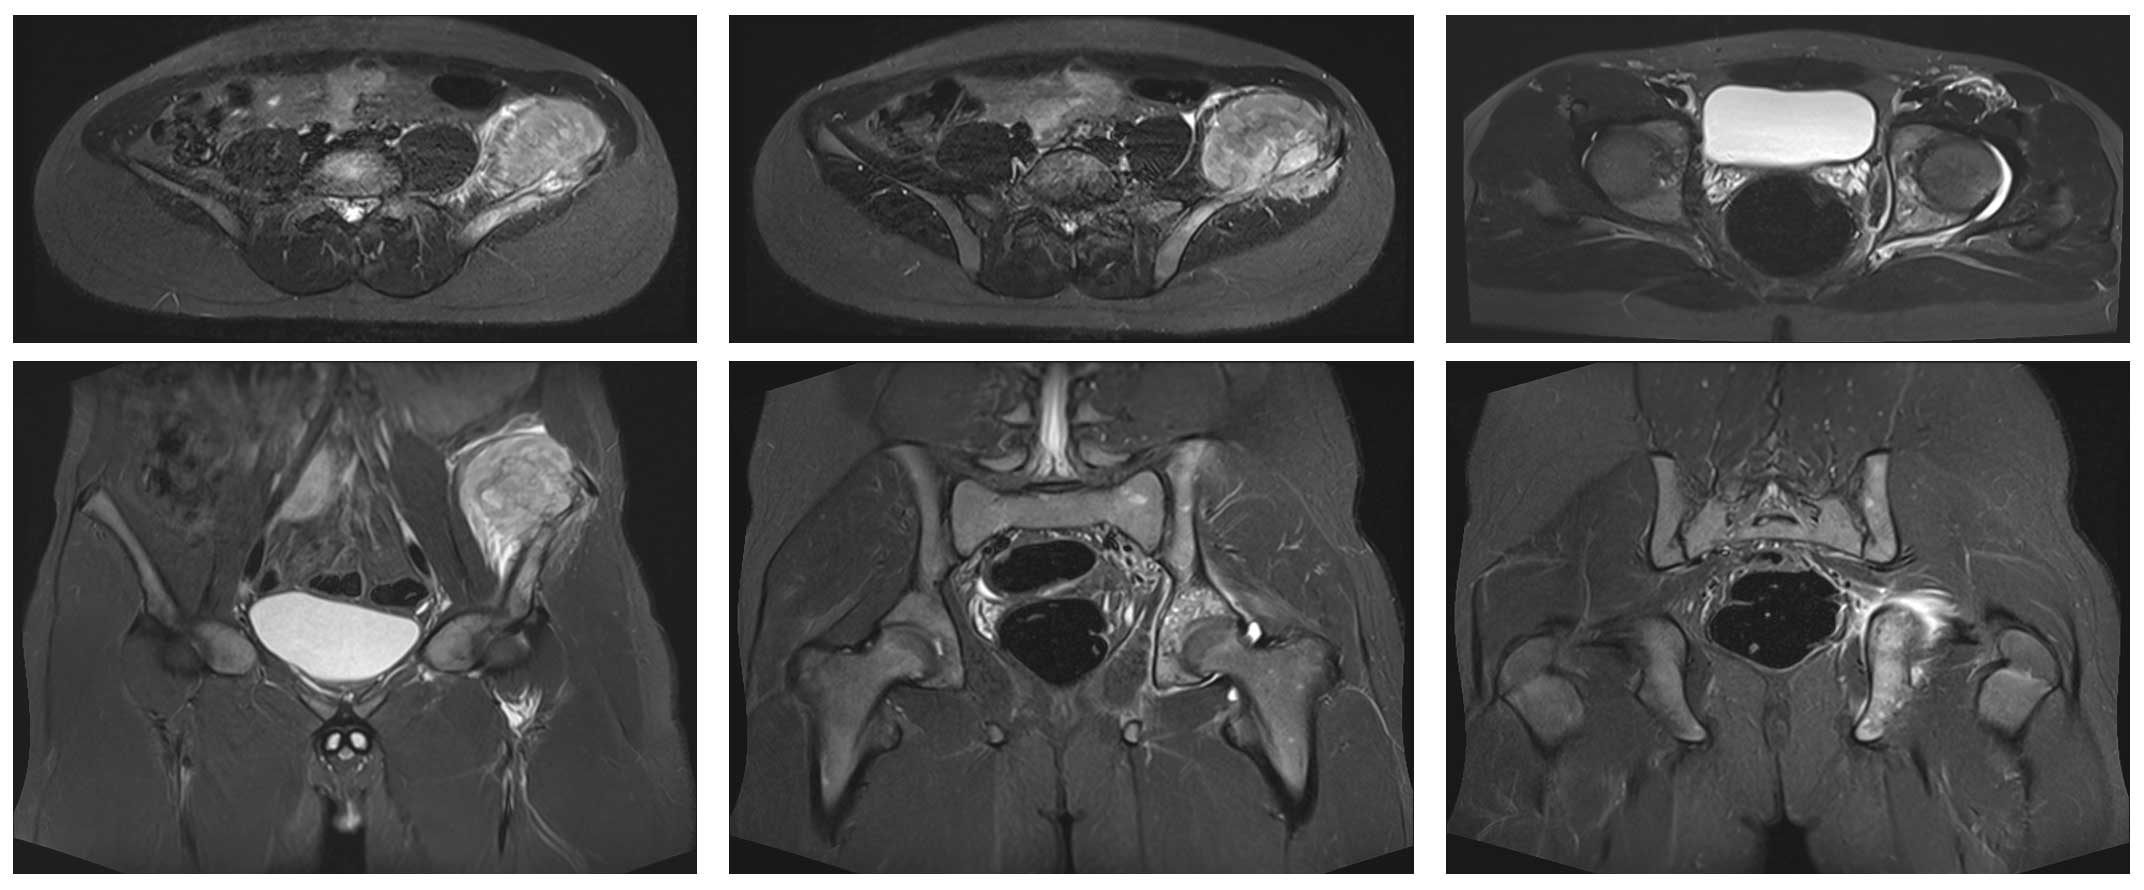

Ameliyat Öncesi: MR’da sol iliak kanatın tamamını içeren yumuşak doku kitlesinin eşlik ettiği tümör dokusu görülmekte.